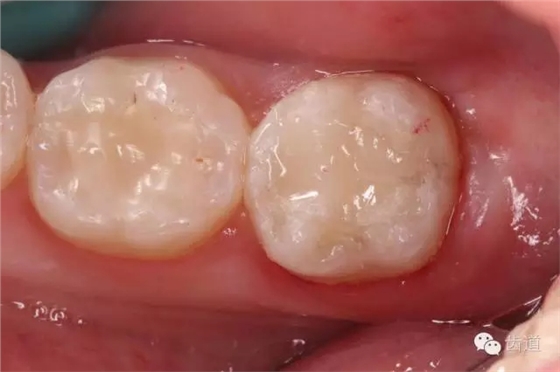

10. 術(shù)后即刻口內(nèi)照片

檢查:術(shù)后半年回訪,37牙體及合面嵌體未見(jiàn)缺損及裂紋,邊緣密合,未探及繼發(fā)齲,探痛-,叩痛-,松動(dòng)-,冷水刺激痛-,未探及牙周袋及附著喪失,牙齦無(wú)紅腫,X線片檢查示根尖周膜連續(xù)性恢復(fù),根尖周透射影消失。

1. 術(shù)后半年口內(nèi)照片